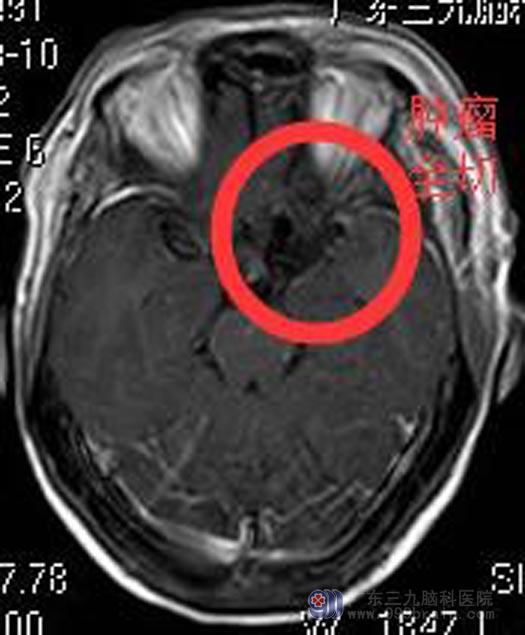

李阿姨和家里人一致要求手术切除治疗,由鲁明主任主刀,在全麻下行左侧鞍旁占位切除术,术中显微镜下见灰白色肿瘤部分裸露,肿瘤质韧,有完整包膜,血供较丰富,镜下全切肿瘤,术中对颈内动脉、大脑中动脉、大脑前动脉、视神经、动眼神经保护完整。

术后李阿姨神志清醒,无功能障碍,经专科治疗护理,康复出院。术后病理回报:脑膜瘤,WHO I级。